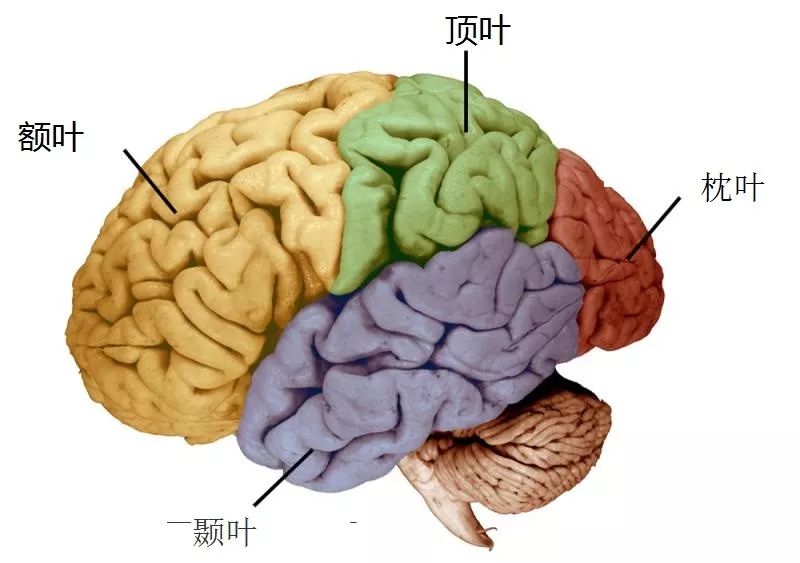

它总共分成四叶:

要描述这四叶分别做什么是件很恼人的事情,因为每一叶都做很多事情,并且互相之间的功能有重叠,但是极端简化的来说:

额叶(frontal lobe)掌管你的人格,以及很多思考相关的东西,比如理论、计划和执行功能。这里要指出,你的很多思考,是在额叶的前端进行的,这部分叫作前额皮质(prefrontal cortex)。前额皮质是那些内心斗争中另一个会出现的角色,那个理性的决策者,那个推动你好好做事的人,那个告诉你不要在意别人想法的真诚的声音,那个希望你能有大格局的领路人。

额叶还负责你身体的运动,额叶最上面的一带,是你的运动皮质。

接着是顶叶(parietal lobe) ,顶叶控制触觉,这一部分功能主要在体感皮质实现,体感皮质在运动皮质旁边。

颞叶(temporal lobe)是你的记忆储存的地方,而因为颞叶离耳朵很近,它也包括了听觉皮质。

头后方的是枕叶(occipital lobe),这里包括了你的视觉皮质,而枕叶几乎是完全为视觉服务的。